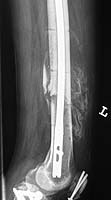

His general condition improved and he returned to the ward after 5 days at the intensive care unit. In the next 2 weeks all the fractures were subsequently treated by internal fixation.  In the left femur retrograde unreamed nailing was performed. Two screws were placed percutaneously in the patella. The tibial plateau fracture was treated by plate and screw osteosynthesis under fluoroscopic control.

Post-operatively, the knee was immediately put on a CPM machine. Despite our functional treatment 2 months after the accident his knee flexion is limited to 70 degrees; knee extension is normal. It is our impression that the flexion is limited by the (palpable) ossification around the femoral fracture. What are your suggestions about further treatment of this problem and how would you improve the knee function?